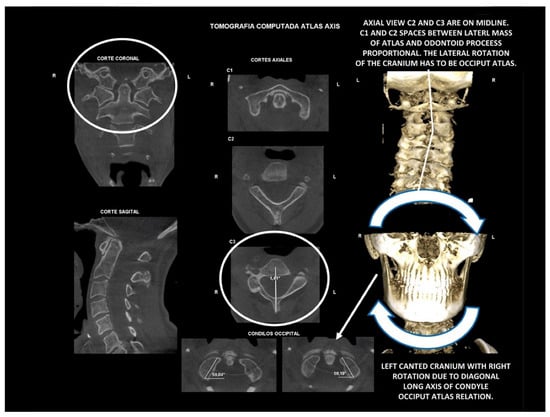

10.2. Computed Tomography of Cervical Spine

11.5. Axis and Atlas Derotation